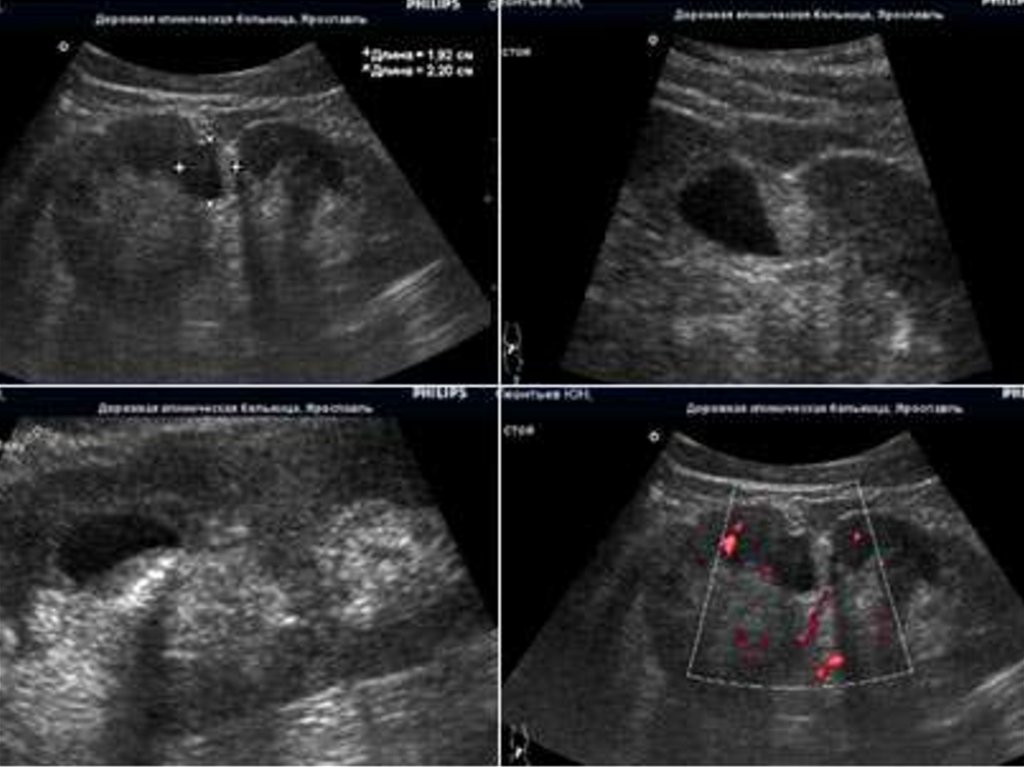

17. Ультразвуковая группа

• Эхоэнцефалография (ЭхоЭГ)

• Ультразвуковая допплерография (УЗДГ)

• Двойная ультразвуковая допплерография

• Транскраниальная допплерография

• Нейросонография

18.

19.

20.